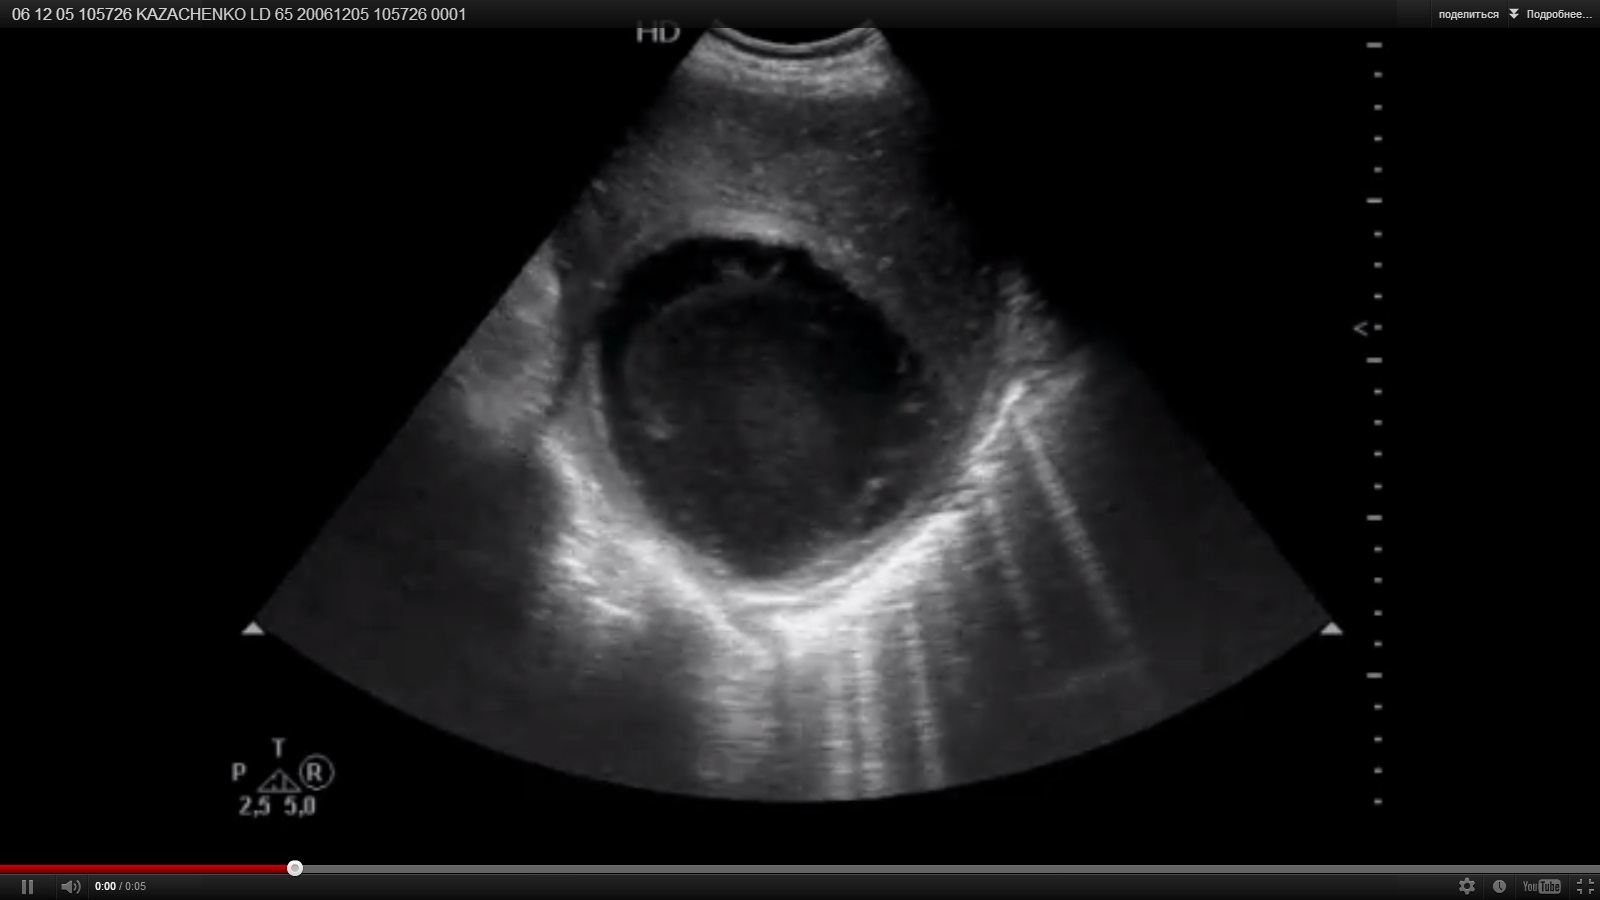

УЗИ: абсцесс печени

Молодой человек. Высоко температурит, бледный.

Абсцесс печени.

тогда уж...абсцессЫ...

Да, абсцессы печени.

БОльший был задренирован, остальные "ушли" на фоне консервативной терапии.

В случае с абсцессом - содержимое акустически непрозрачно + (самое главное)- имеется демаркационный вал паренхимы ("капсула"). Такая семиотика характерна для абсцессов всех паренхиматозных органов.

Паразитарная киста - округлая форма, тонкая капсула (возможна её петрификация), наличие внутри паразита (тонкая лентообразная структура), наличие "дочерних" кист. Где-то на радиографии была хорошая тема про паразитарные кисты печени - могут выглядеть как обычные кисты.